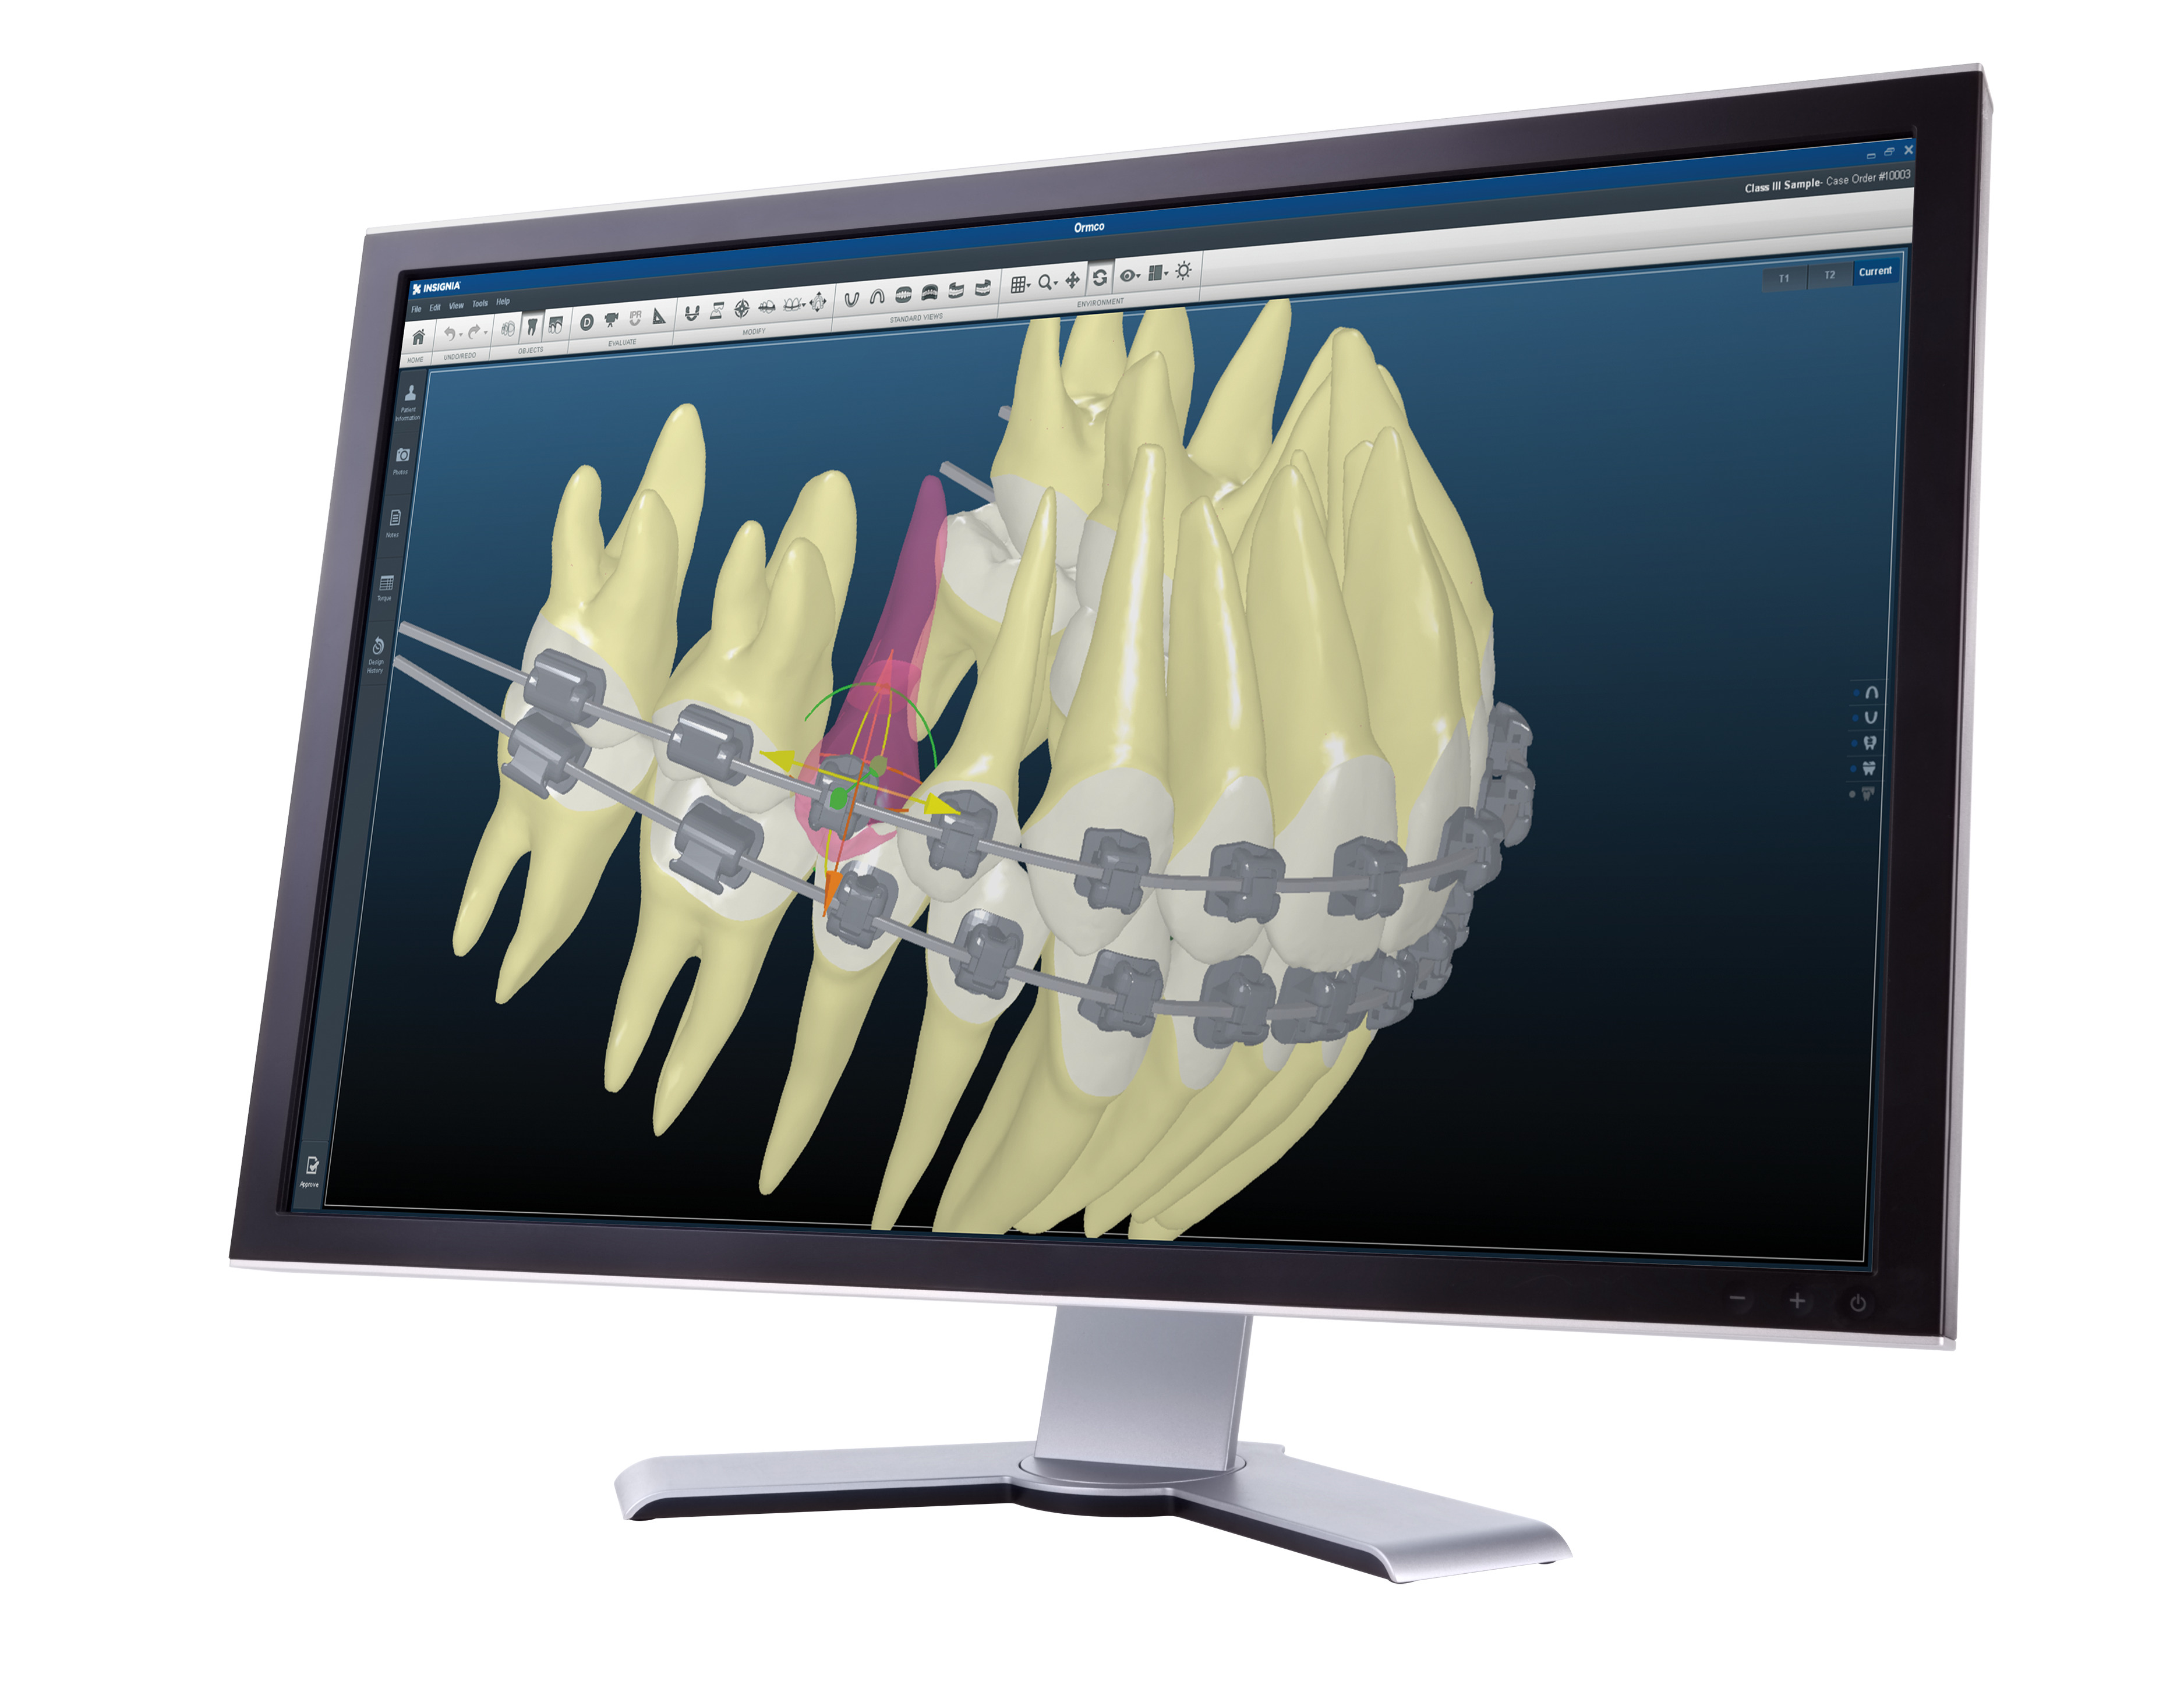

カスタムメイド矯正装置(インシグニア)を使用

インシグニアとは、一人ひとりの口腔内にあわせた効率的なワイヤー矯正治療をコンピュータ上で設計する、オーダーメイドの歯科矯正治療システムです。

インシグニアの導入により、従来の矯正治療と比べて以下のようなメリットを実現しています。

・治療後の歯並びの変化予測を確認できる

・効率的な治療の進行が期待できる

・来院頻度が少なくなる傾向がある

当院では、一部の患者様に、新たなテクノロジーを採用したより正確で負担の少ない治療を提供しております。